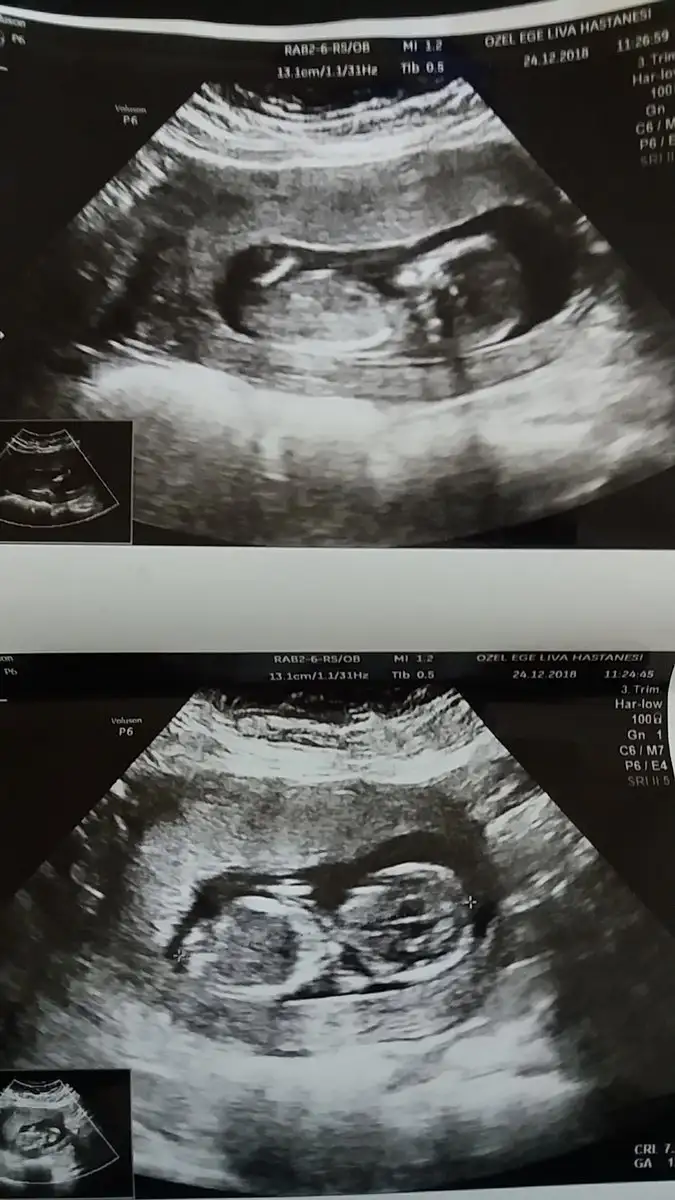

Hanimlar 13+6 dr um cinsiyet belli değil dedi kızlar belli etmez kız mı diye sordum öyle bir şey diyemem dedi bacak arası açık gibi tahmini olan var mi

Kiz gibi pek anlamam ama icime oyle dogdu saglikla gelsin kuzucugunuz :))Bende tahmin alabilir miyim

Erkek gibiSizce bebegimin cinsiyeti nedir?Eki Görüntüle 2214800 Eki Görüntüle 2214800